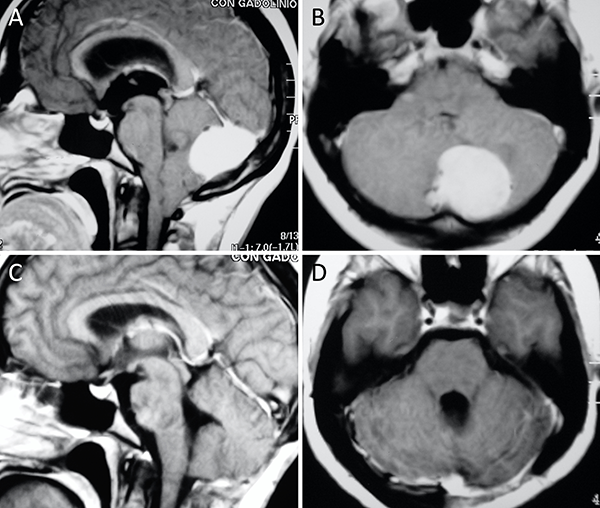

Figura 2. Meningioma tentorial lateral. A-B: RM preoperatoria; C-D: RM postoperatoria.